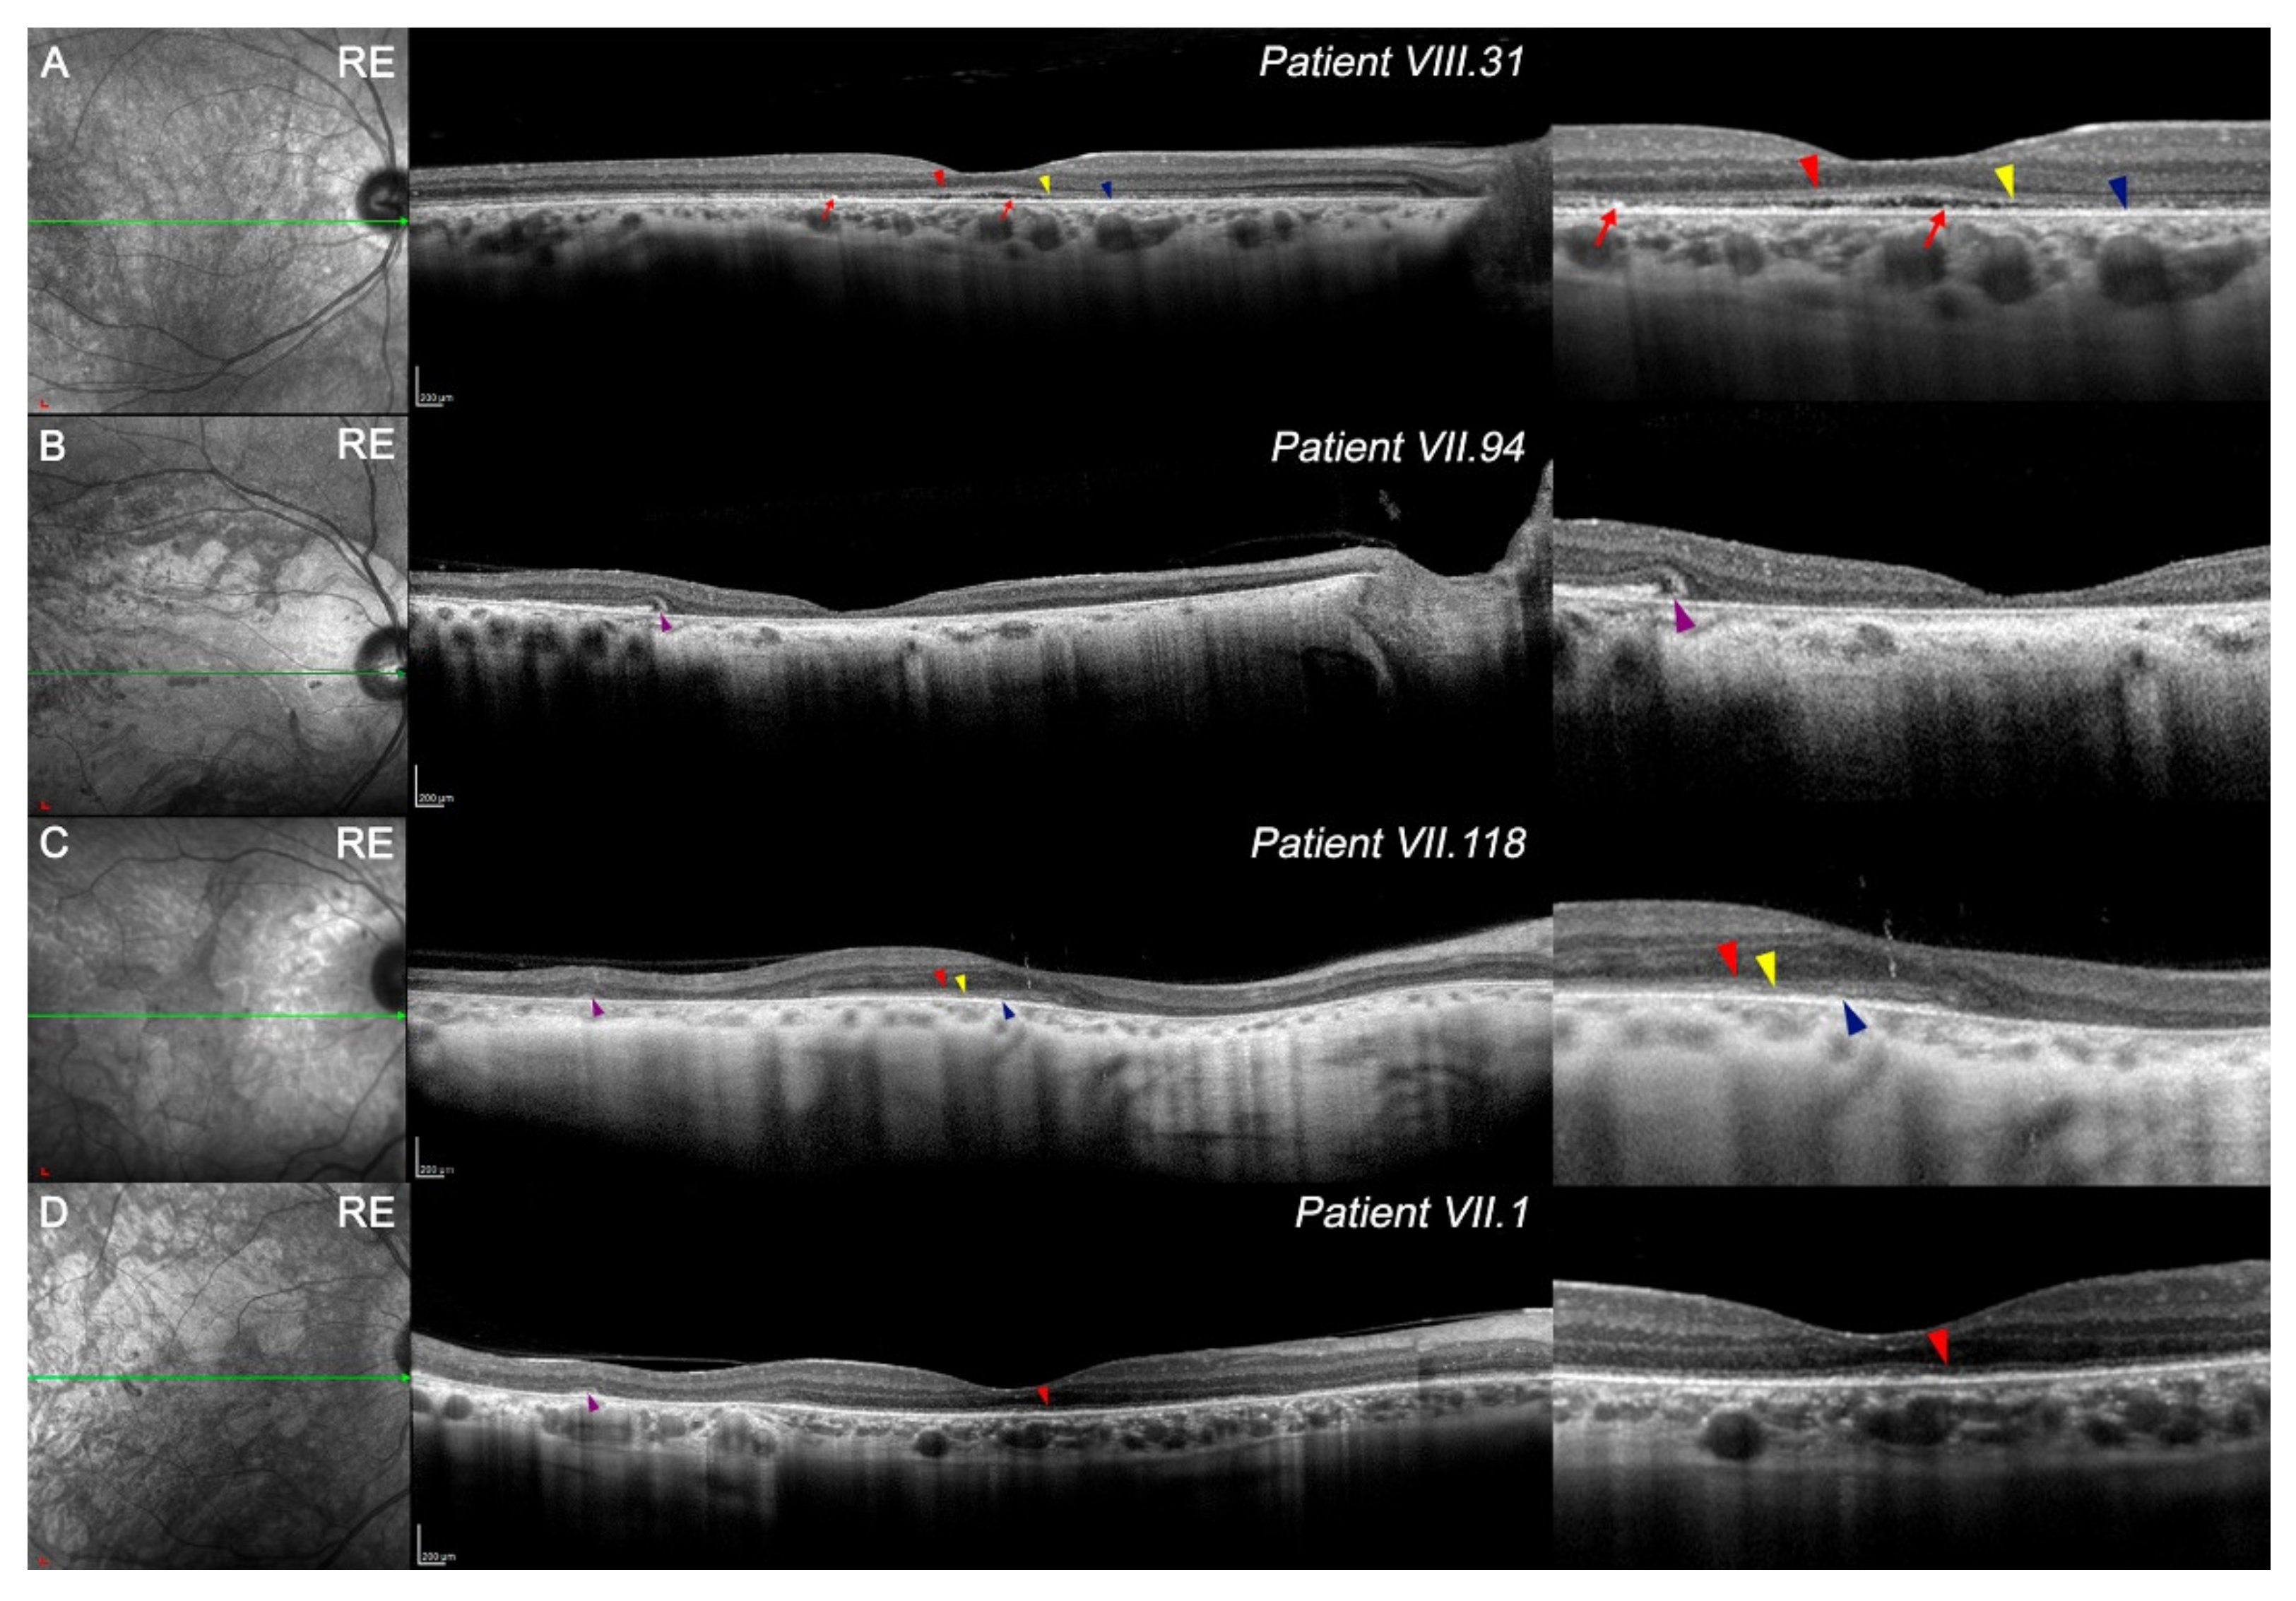

3.3. Features of OCT in CACD Patients: Macular Study and Retinal Tomography

| VIII.31 | 137.7 ± 0.5 | 94 ± 2 | 94 ± 1 | 87 ± 2 | 98 ± 7 | 130 ± 10 | 150 ± 6 | 230 ± 60 | 290 ± 50 |

| VII.94 | 20 ± 20 | 4 ± 5 | 13 ± 2 | 40 ± 20 | 4 ± 8 | 70 ± 10 | 90 ± 10 | 230 ± 50 | 120 ± 50 |

| VII.118 | 173 ± 5 | 120 ± 10 | 30 ± 30 | 30 ± 30 | 20 ± 20 | 110 ± 20 | 145 ± 9 | 140 ± 10 | 140 ± 20 |

| VII.1 | 119 ± 2 | 89 ± 4 | 90 ± 10 | 40 ± 30 | 50 ± 10 | 140 ± 20 | 210 ± 20 | 240 ± 20 | 220 ± 30 |